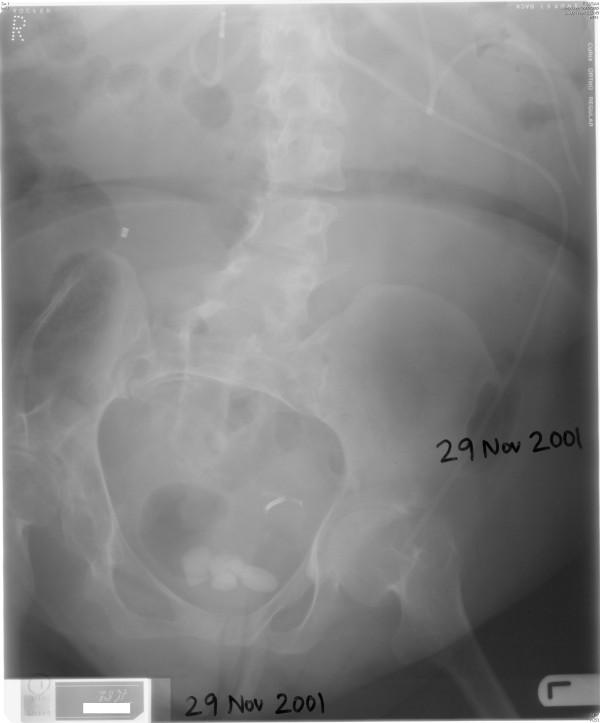

We present a female patient with spina bifida who underwent Benchekroun continent vesicostomy in 1993. This patient developed severe stenosis of Benchekroun stoma and stones in urinary bladder. Dilatation of stoma and vesicolithotomy were carried out in 1995. Vesical calculi recurred; suprapubic cystolithotomy was performed in 1999. In March 2000, catheterisation of stoma was not possible and emergency suprapubic cystostomy was done. In April 2000, endoscopy was attempted through Benchekroun stoma. It was not possible to insert ureterorenoscope beyond two inches. The track was completely blocked. In November 2001, X-ray of abdomen showed several vesical calculi; suprapubic cystolithotomy was performed. In March 2005, this patient developed pain in abdomen. X-ray of abdomen showed a large vesical calculus. In June 2005, suprapubic catheter was removed and a cystoscope was introduced in to the bladder. Then electrohydraulic lithotripsy was performed. In 2007, this patient was concerned about the increasing swelling in lower abdomen. Computed tomography of abdomen revealed midline, lower abdominal wall hernia, which contained several loops of small bowel and ileal cystoplasty. The large hernia was uncomfortable and tender on coughing, but did not cause obstructive bowel symptoms. Surgical repair of hernia was considered. But this patient would require alternative way of urinary diversion because the current location of suprapubic catheter would almost lead to infection of prosthetic material used in reconstruction of the anterior abdominal wall. After discussing risks of operative procedures with patient and her husband, it was decided not to proceed with surgery.

我们报告一名患有脊柱裂的女性患者,她于1993年接受了本谢克鲁恩可控膀胱造口术。该患者出现了本谢克鲁恩造口严重狭窄及膀胱结石。1995年进行了造口扩张及膀胱结石切除术。膀胱结石复发;1999年进行了耻骨上膀胱切开取石术。2000年3月,无法对造口进行导尿,遂进行了急诊耻骨上膀胱造瘘术。2000年4月,尝试通过本谢克鲁恩造口进行内镜检查。输尿管肾镜无法插入超过两英寸。通道完全堵塞。2001年11月,腹部X线显示多个膀胱结石;进行了耻骨上膀胱切开取石术。2005年3月,该患者出现腹痛。腹部X线显示一个大的膀胱结石。2005年6月,拔除耻骨上导尿管并将膀胱镜插入膀胱。然后进行了液电碎石术。2007年,该患者担心下腹部肿胀加剧。腹部计算机断层扫描显示中线、下腹壁疝,其中包含几段小肠和回肠膀胱扩大术。大疝在咳嗽时不舒服且有压痛,但未引起肠梗阻症状。考虑进行疝修补手术。但由于耻骨上导尿管的当前位置几乎会导致用于重建前腹壁的假体材料感染,该患者需要替代的尿液转流方式。在与患者及其丈夫讨论手术风险后,决定不进行手术。